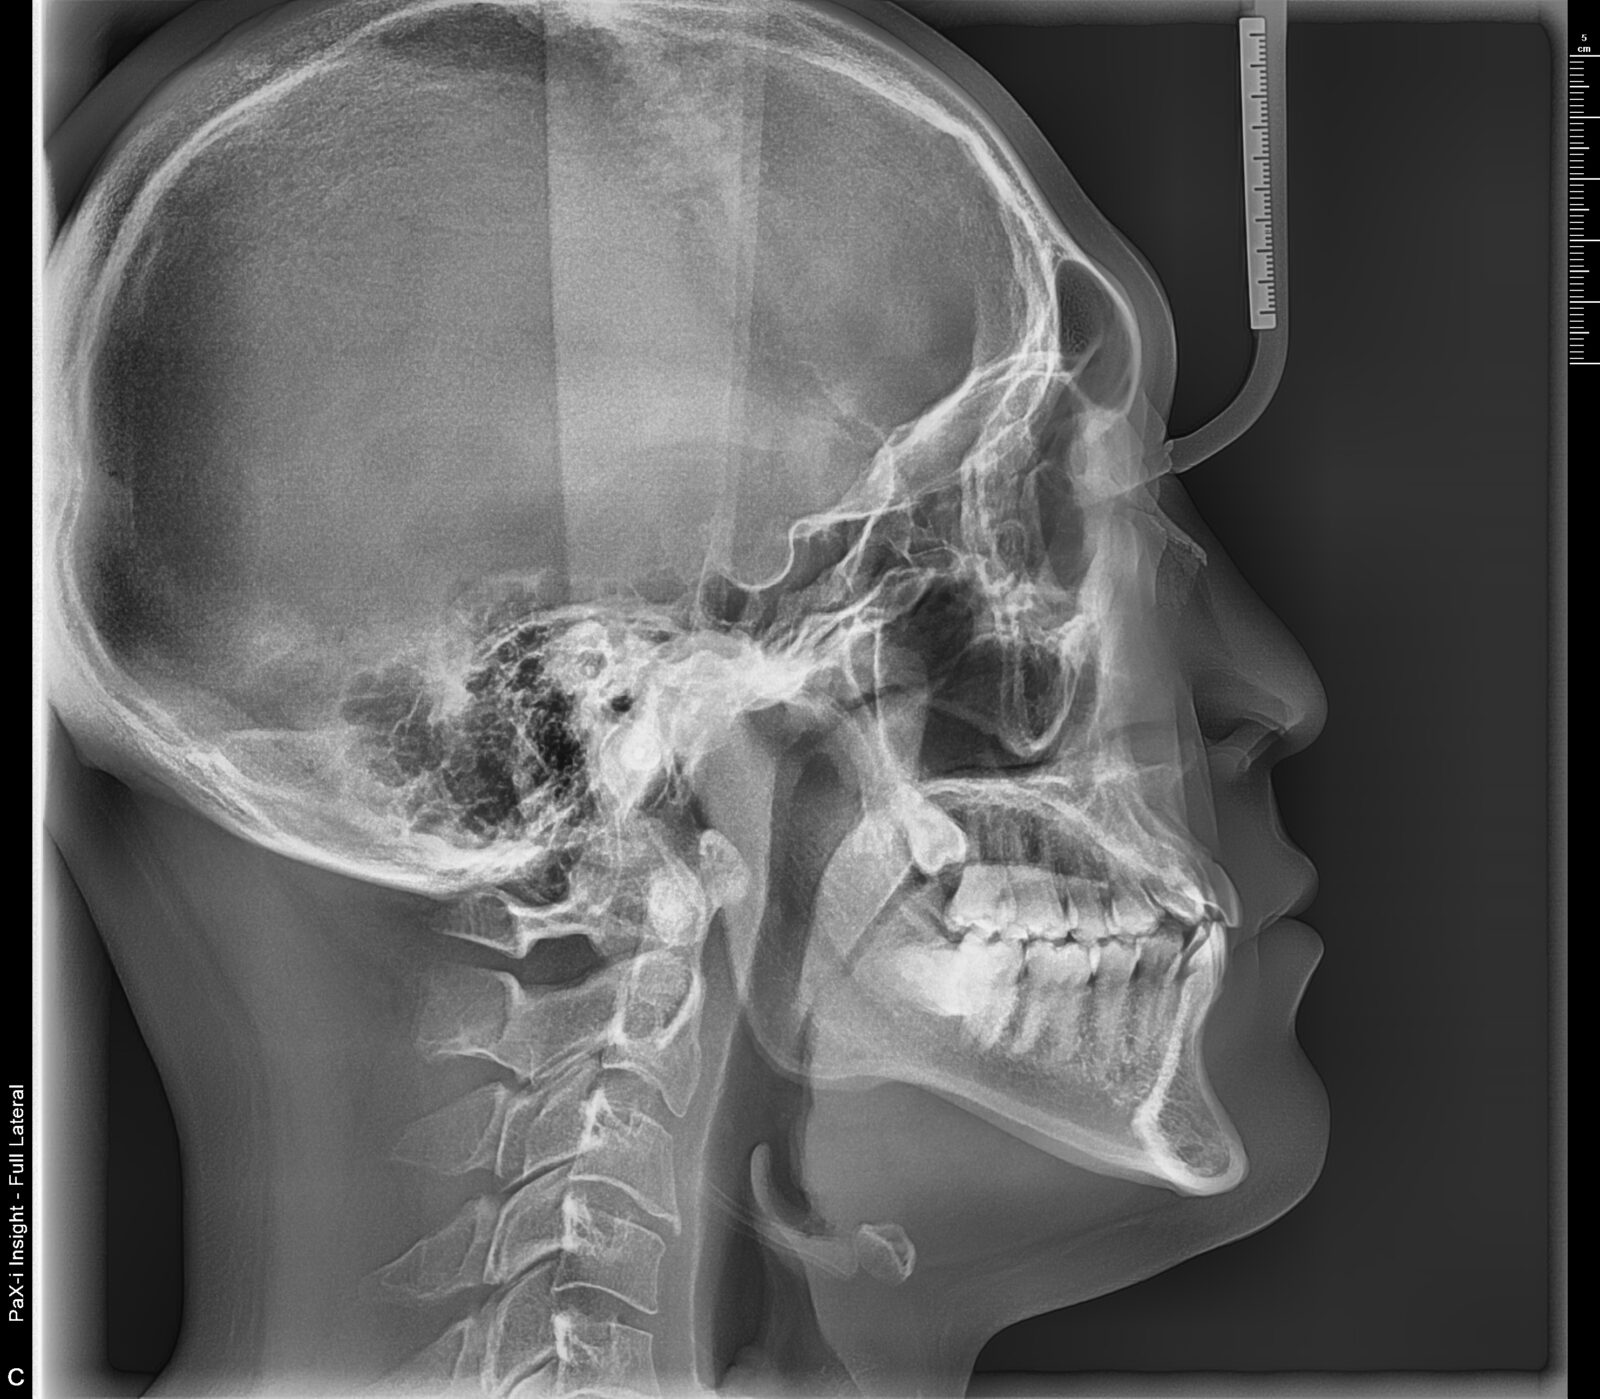

リテーナー不使用と、定期メンテナンス通院中止による後戻りの改善の症例

正中も揃った。ワイヤー矯正前の歯列は前歯が出ていたとのこと。

上顎前歯の唇側の骨の厚みを確保すると安定してくるが、側方への外力をコントロールし、適度な垂直圧が維持される必要がある。

舌癖や、舌のポジションを含む習癖や習慣的な体の使い方の工夫が必須。

コンパクトな費用のプランを選択されたため出来なかったが、本当は6番、7番も微修正したいところ。

主訴は前歯だったが、小臼歯まで移動範囲に加えてバランスを整えていった。

定期メンテナンスの際に姿勢を含む習癖の改善のアプローチを行なった。

初診時と比較し、自然と骨格のズレも修正されていった。

首の歪みも確認できるようになった。

過去、非抜歯ワイヤー矯正をしたが、リテーナー不使用等による後戻りを改善したいとの要望に応える。

・費用:456,500円(税込) ※リテーナー別途

・治療期間:7ヶ月 (ステージ数:上顎9、下顎13+追加アライナー上顎9、下顎11)

・使用装置:インビザラインGO

・女性

・オプション:エアフロー